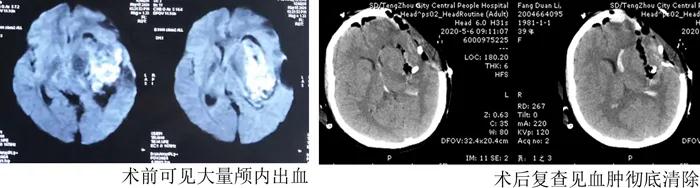

此刻,手術(shù)室氛圍異常緊張,但隨著手術(shù)的進(jìn)行,顱內(nèi)血腫在顯微鏡下被一點(diǎn)點(diǎn)清除,盡可能保護(hù)住了周圍正常腦組織,減少正常血管出血。逐漸探明畸形血管大致形態(tài)及位置后,將血腫徹底清除,并迅速把周邊畸形異常血管切除,妥善止血,于凌晨1點(diǎn)順利結(jié)束手術(shù)。

雖然手術(shù)順利,但患者暫時(shí)仍未脫離生命危險(xiǎn),決定將患者轉(zhuǎn)入重癥監(jiān)護(hù)室繼續(xù)救治。早已在監(jiān)護(hù)室等候的朱思良醫(yī)生和產(chǎn)科顏曉華大夫迅速對(duì)產(chǎn)婦進(jìn)行了全面細(xì)致的評(píng)估,并制定了周密的治療方案。在隨后5天的精心治療和護(hù)理中,產(chǎn)婦逐漸恢復(fù)了意識(shí),肢體活動(dòng)部分恢復(fù),復(fù)查顱腦CT見(jiàn)血腫完全清除。5月10號(hào)母親節(jié),在這個(gè)特殊的日子,患者脫離生命危險(xiǎn)轉(zhuǎn)到普通病房,終于見(jiàn)到了焦急等待的丈夫和轉(zhuǎn)危為安的女兒!